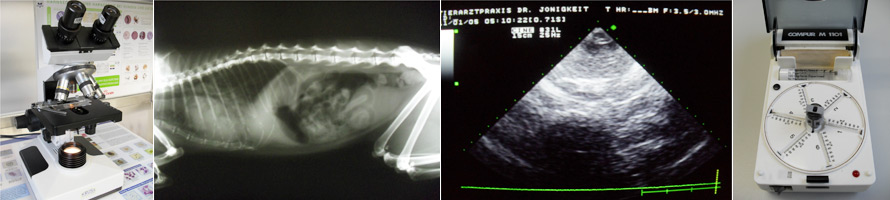

Allgemeine Leistungen | Diagnostische Hilfsmittel | Chirurgie | Anästhesie | Spezielle Leistungen